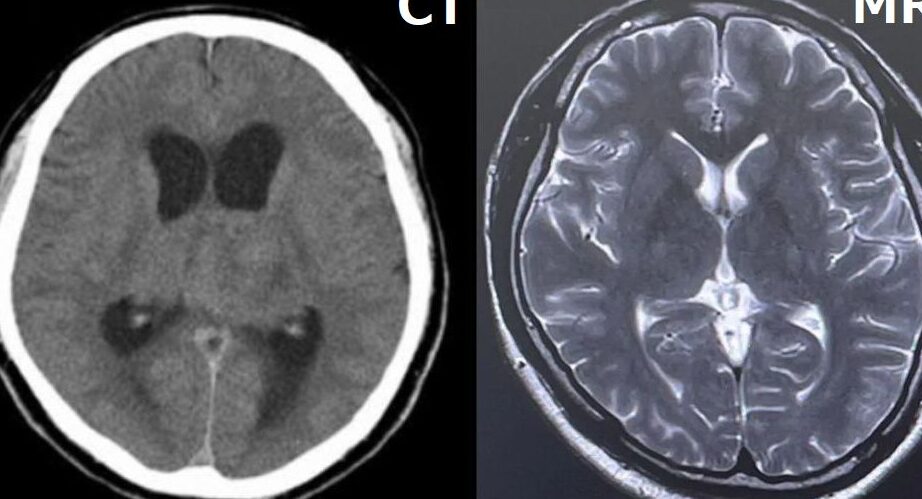

CTとMRIは、異なる画像取得技術を利用して体内の画像を生成する。これらの技術はそれぞれ特性があり、用途も異なる。

画像取得方法の違い

CTはX線を使用して断面画像を作成する。数秒で画像を取得し、迅速な診断が可能。MRIは強力な磁場と無害な電波を使用するため、放射線の影響を受けない。画像を取得する際に身体全体をスキャンするため、詳細なソフトティッシュの情報が得られる。